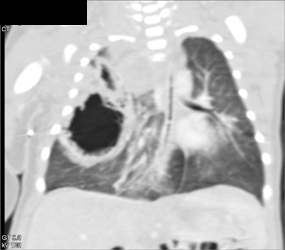

Pulmonary Embolism